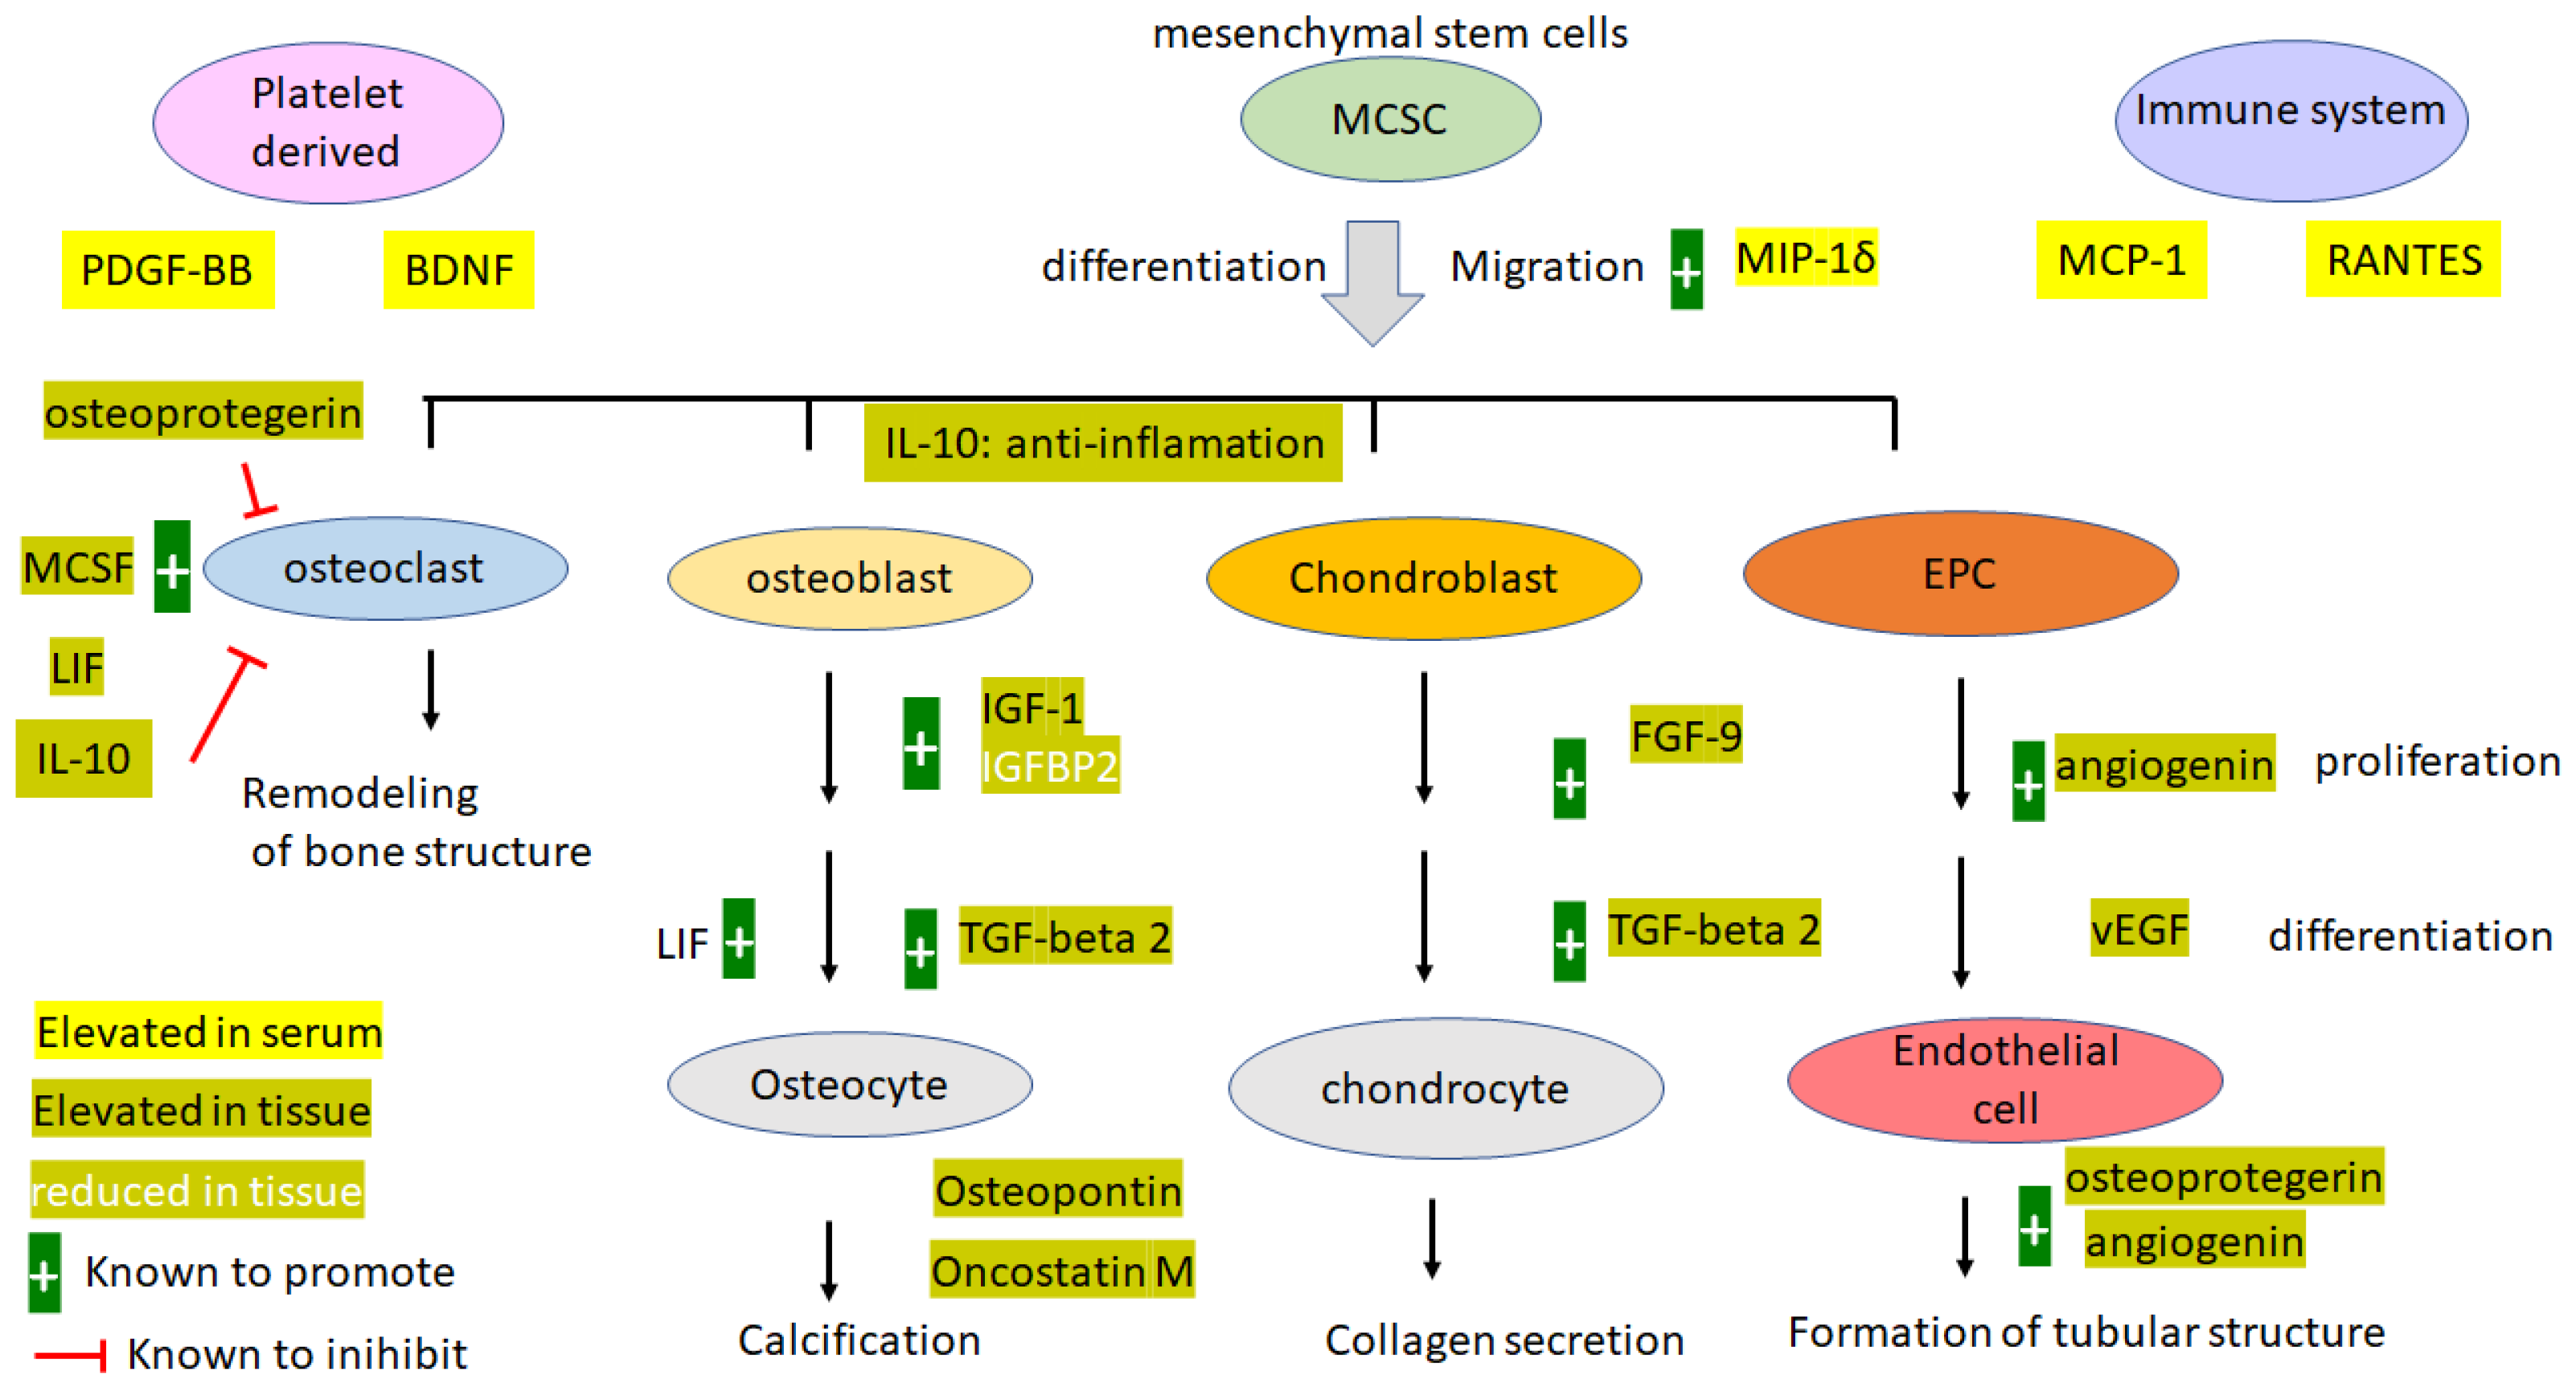

4. Discussion

4.1. Pathology and Etiology

4.4. Angiogenesis Factors: ANG, vEGF, and Osteopretegerin

4.5. Systemic Inflammation cf Local Inflammation

4.6. Platelet-Derived EGF, PDGF-BB, and BDNF

4.7. Bone Formation-Promoting Proteins

4.8. Osteopontin (OPN)

4.9. Osteoprotegerin OPG

4.10. IGF-1 and IGFBPs

5. Conclusions